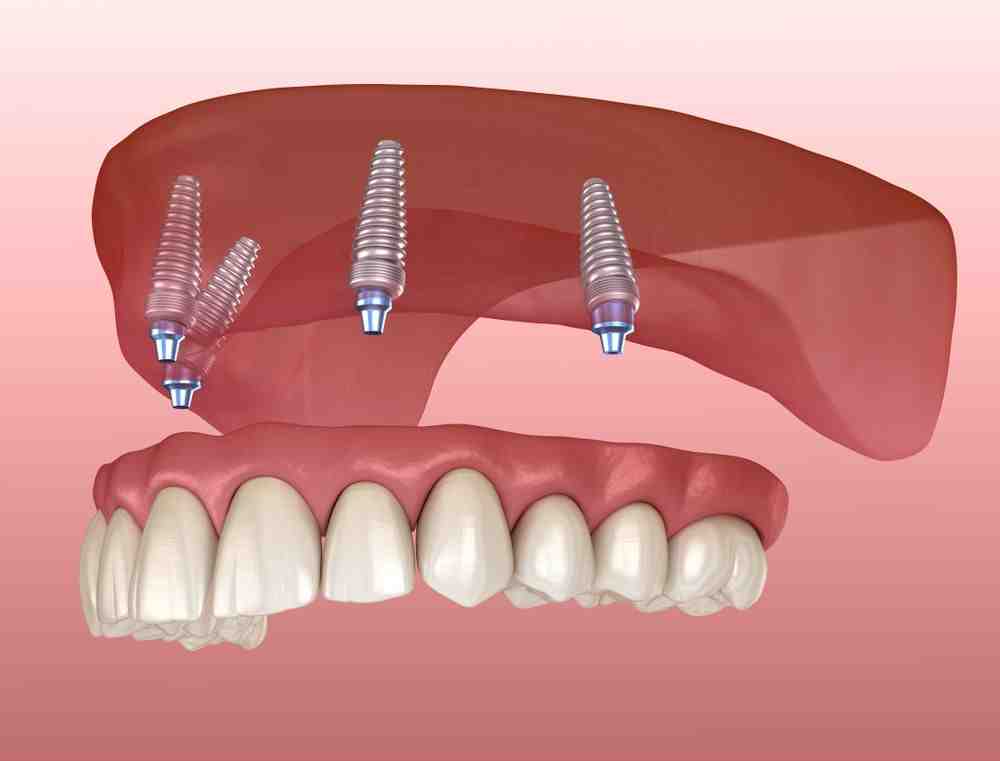

How long do full mouth dental implants last?